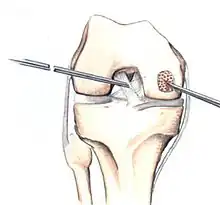

The articular cartilage along the border of the osteochondritis dissecans lesion

Arthroscopic image of OATS surgery on the medial femoral condyle of the knee

The choice of surgical versus non-surgical treatments for osteochondritis dissecans is controversial.[51] Consequently, the type and extent of surgery necessary varies based on patient age, severity of the lesion, and personal bias of the treating surgeon—entailing an exhaustive list of suggested treatments. A variety of surgical options exist for the treatment of persistently symptomatic, intact, partially detached, and completely detached OCD lesions. Post-surgery reparative cartilage is inferior to healthy hyaline cartilage in glycosaminoglycan concentration, histological, and immunohistochemical appearance.[52] As a result, surgery is often avoided if non-operative treatment is viable.